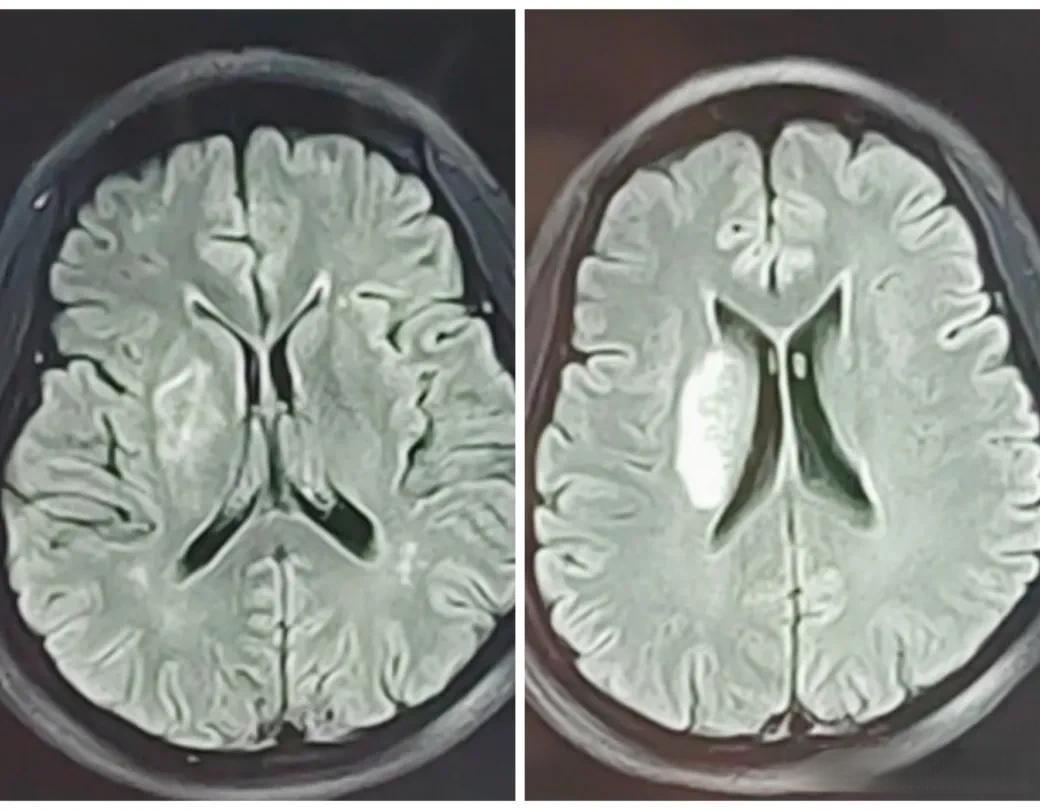

一位65岁的男性患者在半个月内连续两次突发脑梗死,第二次发作时症状更加严重。医生表示,如果第一次发作时及时进行溶栓治疗,可能就不会有第二次发作。这个罕见的案例再次凸显了溶栓治疗在急性脑梗死中的重要性。